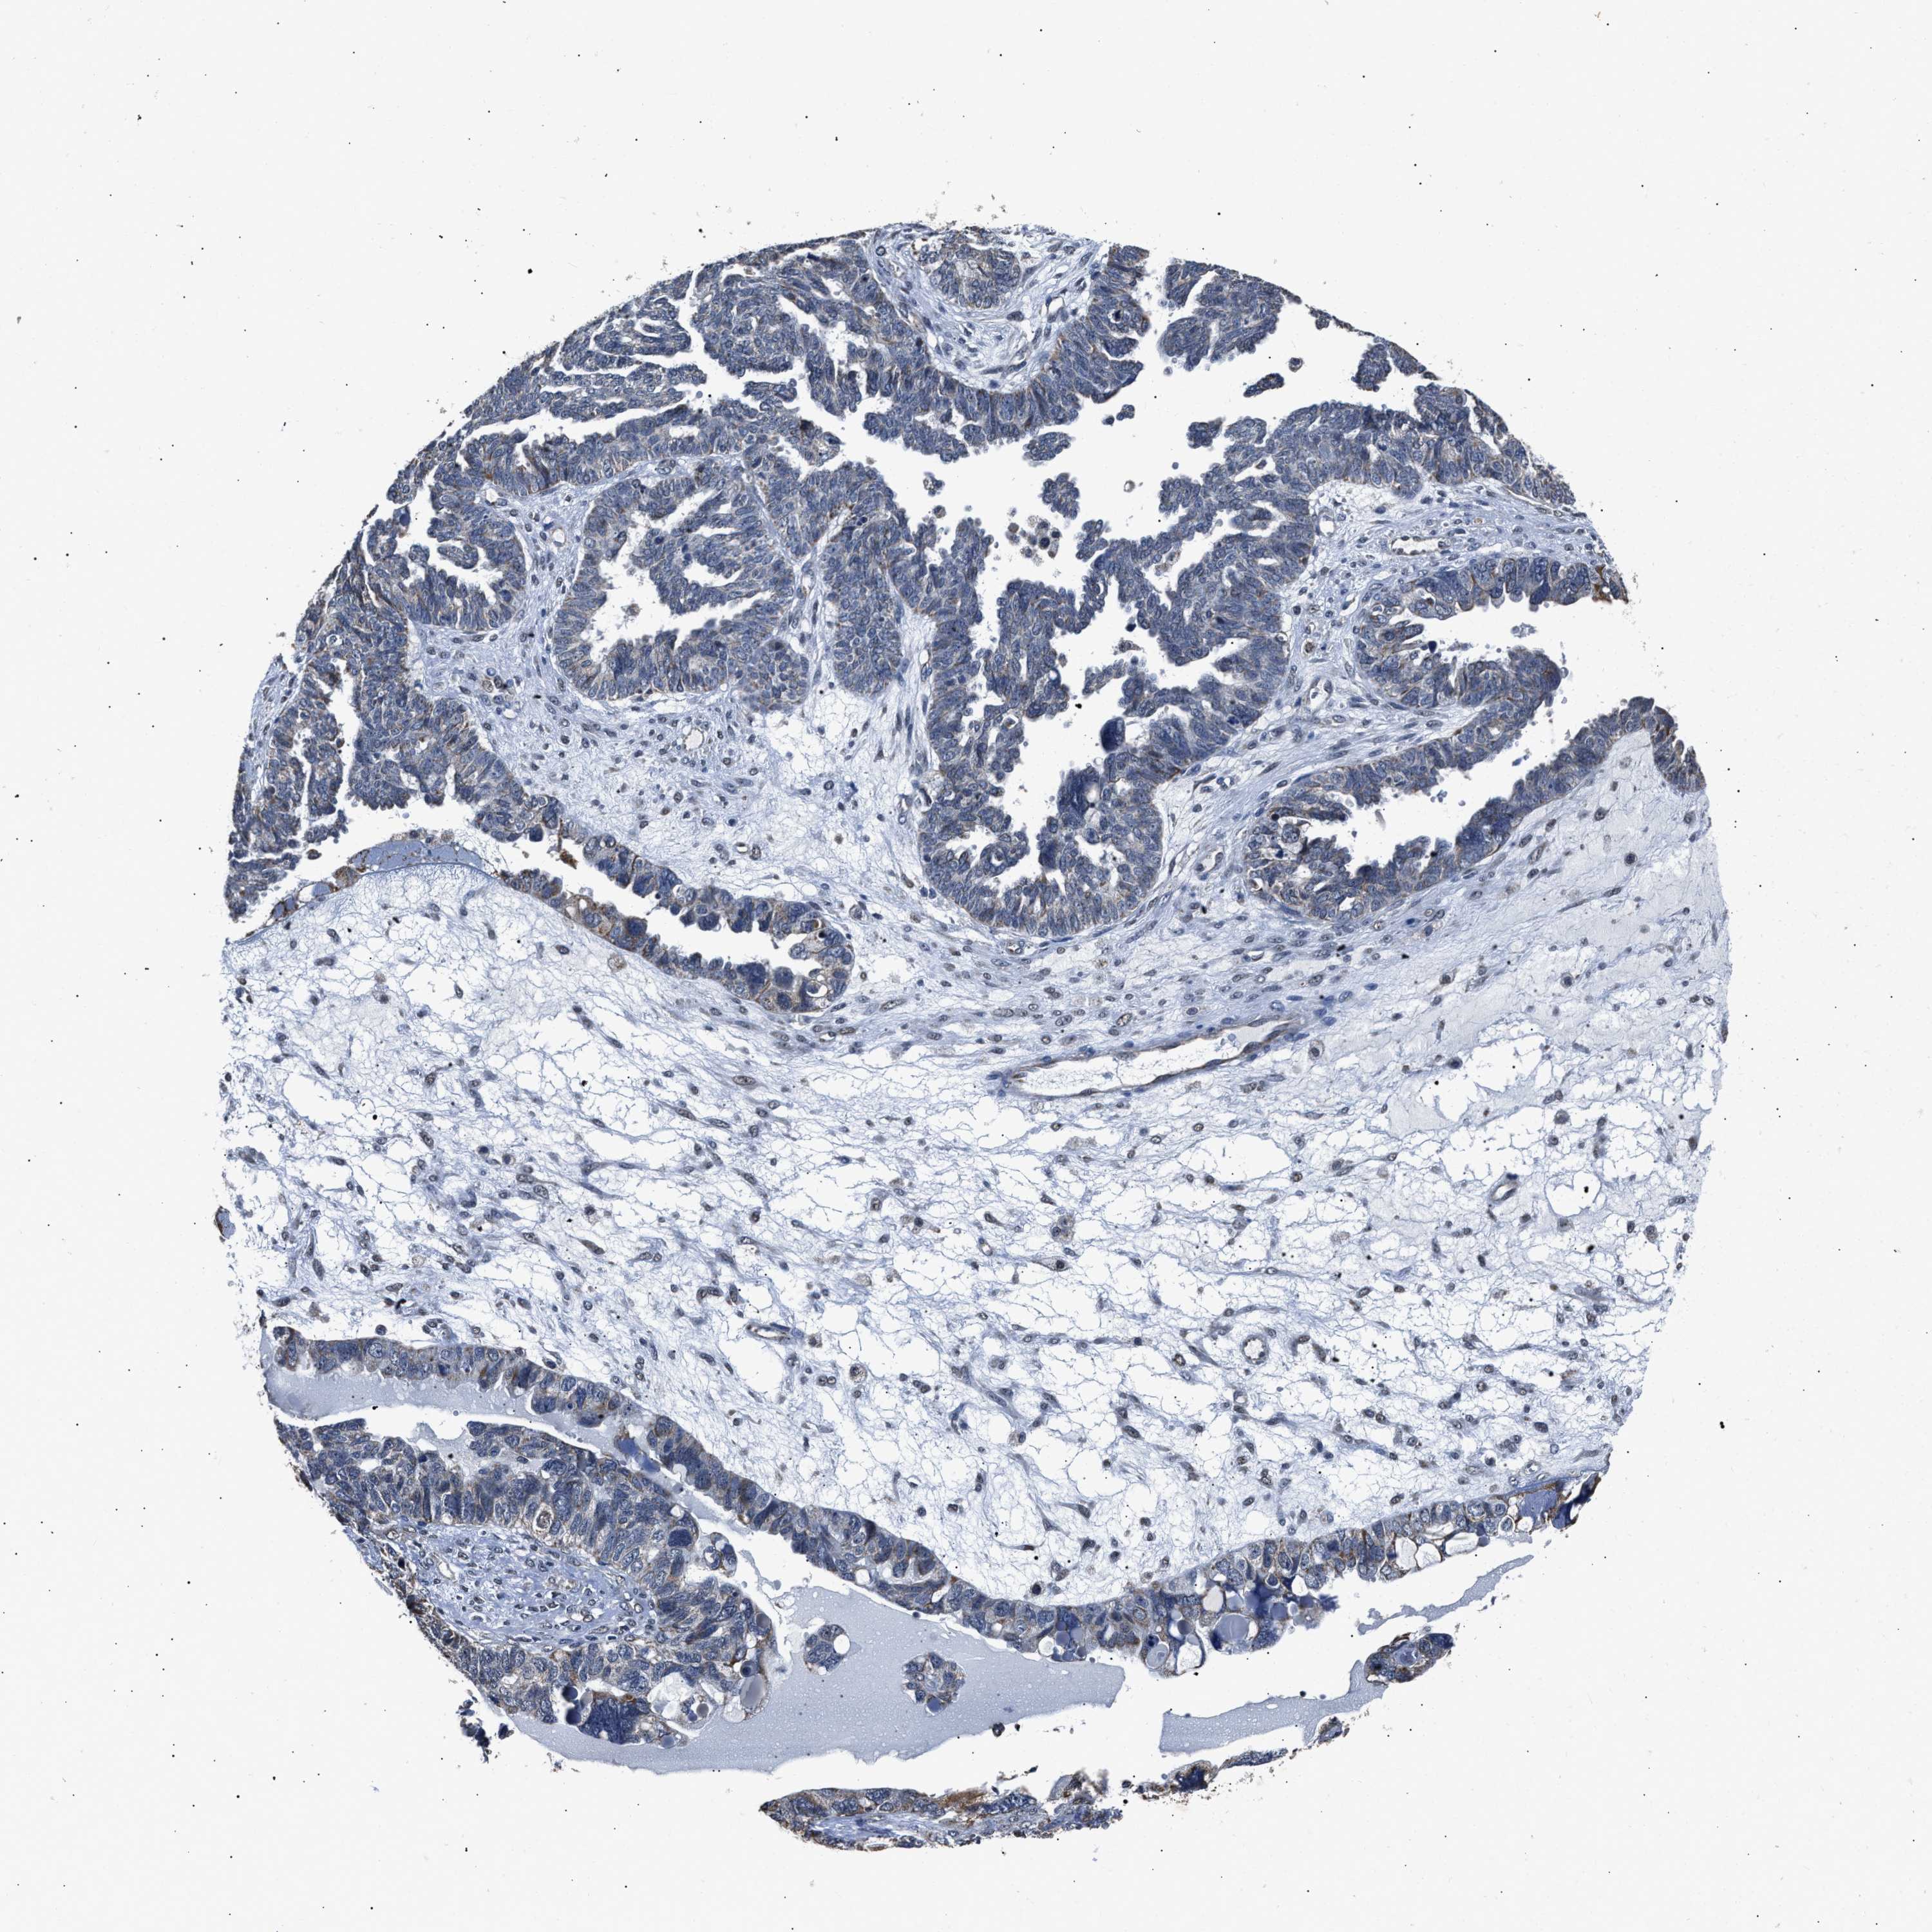

OVARIAN CANCER - Protein expressioni

A mouse-over function shows sample information and annotation data. Click on an image to view it in a full screen mode. Samples can be filtered based on level of antibody staining by selecting one or several of the following categories: high, medium, low and not detected. The assay and annotation is described here.

Note that samples used for immunohistochemistry by the Human Protein Atlas do not correspond to samples in the TCGA dataset.

Antibody stainingi

Antibody staining in the annotated cell types in the current human tissue is reported as not detected, low, medium, or high, based on conventional immunohistochemistry profiling in selected tissues. This score is based on the combination of the staining intensity and fraction of stained cells.

Each image is clickable and will lead to virtual microscopy that enables deeper exploration of all samples and also displays staining intensity scores, fraction scores and subcellular localization as well as patient and tissue information for each sample.

Antibody HPA020536

Staining

High

Medium

Low

Not detected

Intensity

Strong

Moderate

Weak

Negative

Quantity

>75%

75%-25%

<25%

None

Location

Nuclear

Cytoplasmic/membranous

Cytoplasmic/membranous,nuclear

Cystadenocarcinoma, serous, NOS

Carcinoma, endometroid

Cystadenocarcinoma, mucinous, NOS

Carcinoma, NOS